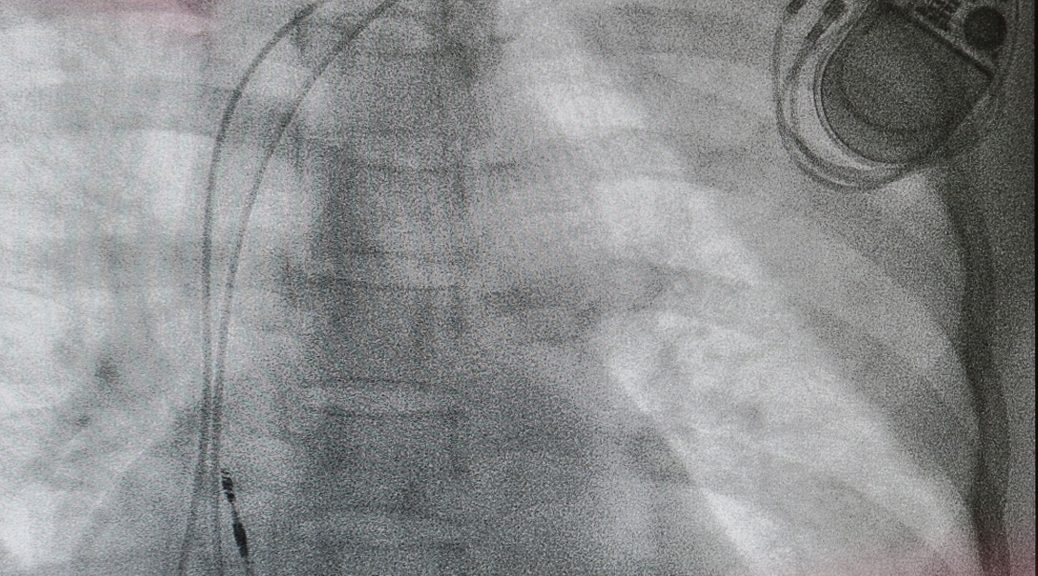

Cụ L. T. V 93 tuổi (Vĩnh Phúc) đến Trung tâm tim mạch bệnh viện Đông Đô thăm khám. Cụ được chẩn đoán bị xơ vữa động mạch ngoại biên (PAD rutherford V).Tại chân phải, hẹp vừa lan tỏa động mạch đùi nông, hẹp khít ½ trên động mạch chày trước, tắc hoàn toàn động mạch chày sau.

Đối với trường hợp của cụ V, các bác sĩ đã thực hiện thủ thuật can thiệp qua da, mở lại động mạch và làm phẳng khối tắc vào thành động mạch, đồng thời kéo căng động mạch mở để tăng lưu lượng máu.